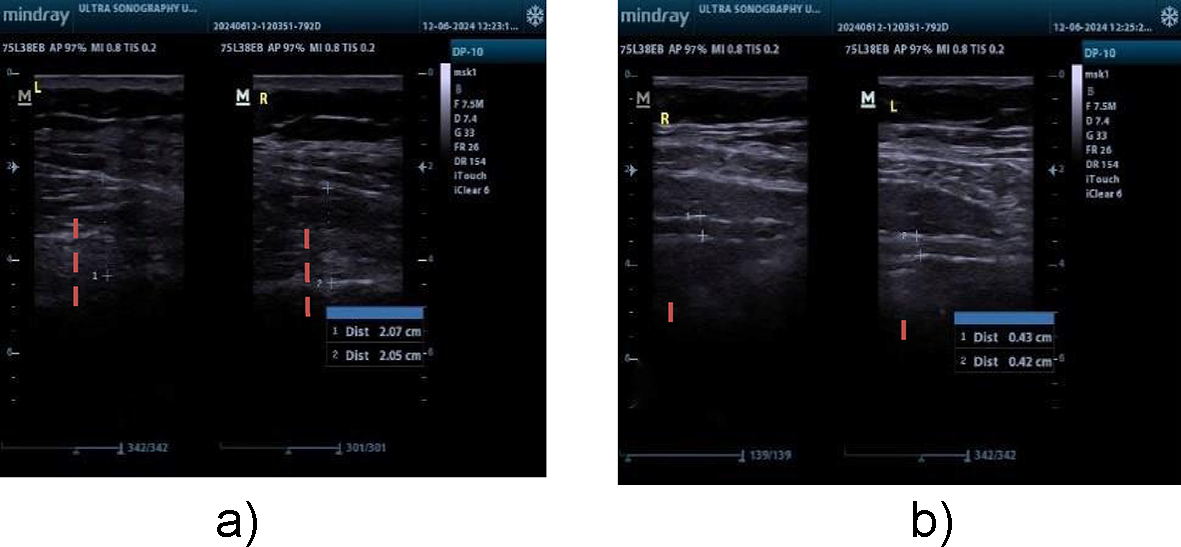

(a) LM thickness measurement, (b) TRA thickness measurement.